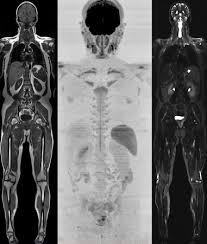

Premium Full Body Scans

Premium full body scans provide a comprehensive assessment of your health using advanced diagnostic technologies to detect potential issues before symptoms appear. Depending on the clinic and your health priorities, these programs may include procedures such as endoscopy, colonoscopy, and advanced 3D imaging to evaluate key organs and systems with exceptional precision.

Premium Cancer Scan (Tokyo)

Comprehensive full body scan with the latest technologies for cancer screening.

AI-diagnostics for Tumors

Full Body MRI

Endoscopy + Colonoscopy

Advanced Blood Tests